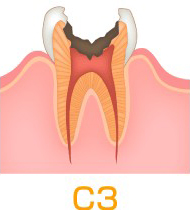

さらにその奥の神経まで感染すると(C3)、痛みを伴うようになります。感染した神経を取り除き清掃する根管治療が必要となり、歯を長持ちさせるためにも重要な治療になります。

歯の神経までむし歯が到達した状態。

ズキズキ痛かったり噛むと痛い症状が出るが、症状がでていないこともある。

▶︎治療法:抜歯処置と歯冠修復が必要